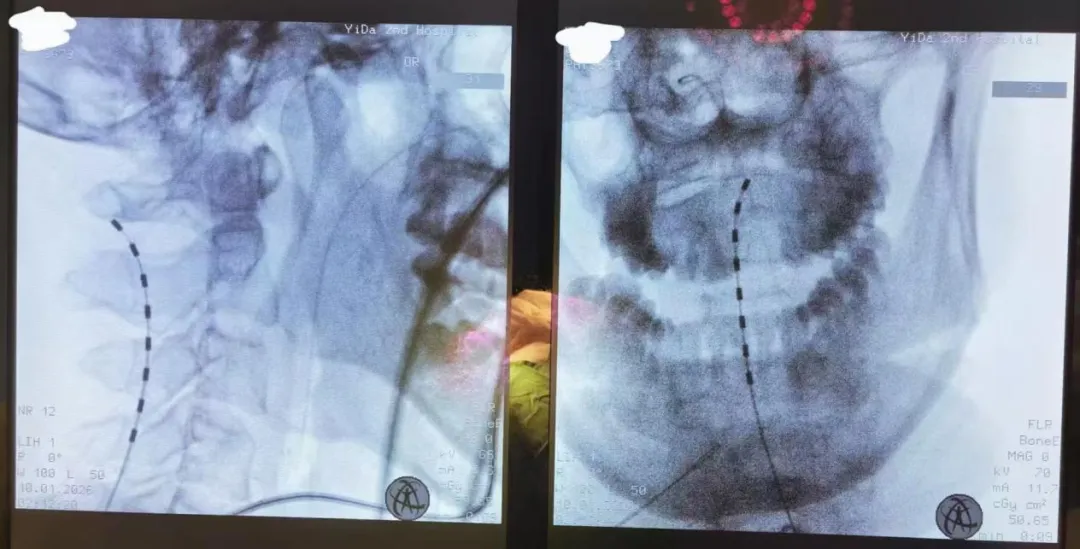

术中,李文玲团队在精准影像引导下,将电极植入脊髓硬膜外,通过特定参数电刺激,激活上行网状激活系统及相关神经网络,促进神经功能重塑。